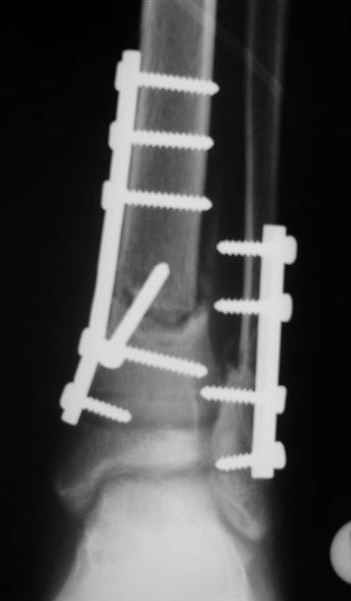

АВФ -отдельная история в нашем краю, поэтому последний вариант -открытая репозиция, что я и сделал: Без мобилизации отломков б.б. репозиция м.б. не получалась. Первым делом фиксировал перелом м.б. кости пластиной на 4 4,5 мм винтах,

при ревизии зоны перелома б.б. кости сохранялось смещение дистального отломка кпереди, пришлось принять меры и решить эту проблему.

На прямой проекции видно угловое смещение отломков малоберцовой кости, обуславливающий и

наклон тарана, да и вальгус отломков б.б. , а на боковой проекции -смещение отломков

кпереди и по длине.

Коррекция углового смещения и смещения по длине отломков м.б. кости автоматом устраняет

наклон тарана , что необходимо для нормальной функции голеностопа. Так оно и произошло во

время операции.

Единственный момент, о котором я и уже писал - не наступило спонтанной анатомичной

репозиции отломков б.б., поэтому после репозиции пришлось использовать тягловый винт и

*укрепить* достигнутое положение узкой пластиной динамической компрессии.

Послеоперационные снимки сегодня посмотрел - все выглядит вполне анатомично, кроме длины

винтов на м.б. кость - слегка переборщил:-(( Не было камеры с собой , но как только

пересниму картинки обязательно вышлю.

Поэтому фиксация м.б. кости все-таки показана....

Помятуя наш недавний разговор о фиксации м.б. кост, высылаю послеоперационные картинки..

Напомню- разбирали случай 17 летнего молодого человека перелом дист тиб.фиб. хирургия после 3 недель с момента травмы( безуспешные попытки закрытой репозиции) Раны заживают первичным натяжением, занимается физиотерапией, пока никаких проблем не наблюдается